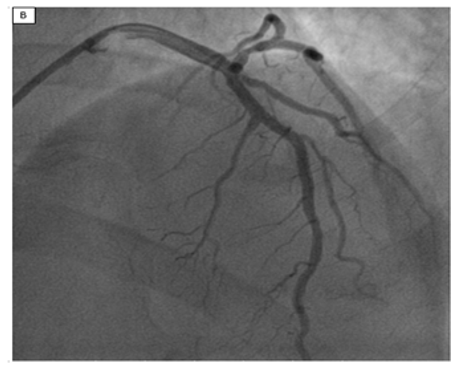

Figure B: LAO Cranial View Demonstrating LAD Stenosis with under Expansion of 2.75 x 38 mm DES

DES was sub-optimally expanded after standard deployment compared with nominal sizes. Post-dilatation using 2.75 x 12 NCBs following 3 x 6 mm NCB and 3.25 x 8 mm NCB was performed. Unfortunately, LAO cranial view still demonstrated DES under expansion. In this setting Rotational atherectomy, RA and OA were contraindicated for intrastent treatment. At the contrary intravascular lithotripsy (IVL) was indicated.